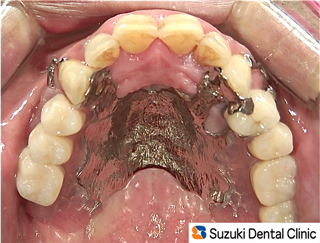

50代の男性。主訴は「奥歯がほとんど無いので、出来るだけ違和感の少ない入れ歯をお願いします。」

でした。

当院では、保険の入れ歯(プラスティック製)でも出来る限り薄い入れ歯を作製していますが、”薄く”には限界があります。その点、メタルで作られた保険外の入れ歯=写真=は「薄くて(厚み1㎜)、割れない丈夫な入れ歯」といえます。この患者様は、嘔吐反射の癖をお持ちでしたが、新しい入れ歯を装着した初日から「嘔吐(えず)かず、痛まず、いいよ!」と嬉しいコメントをいただきました。 続きを読む